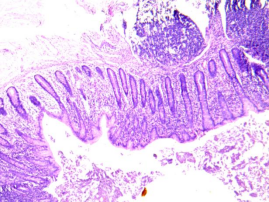

化脓性阑尾炎

阑尾表面有灰白色脓性渗出物,腔内充满中性粒细胞,各层有大量中性粒细胞浸润及充血水肿。

管壁全层大量中性粒细胞浸润